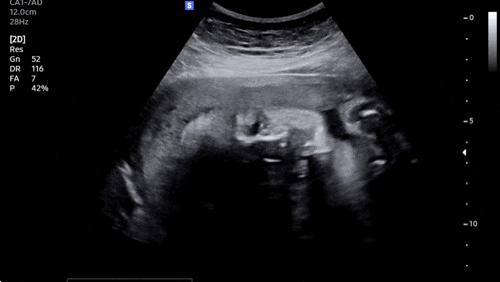

?37주차 증상? 1) 양수검사 늘 넘쳐나던 양수가 줄어들엇다고 하셨다!!! 네?!!!! 안암고대병원에서도...